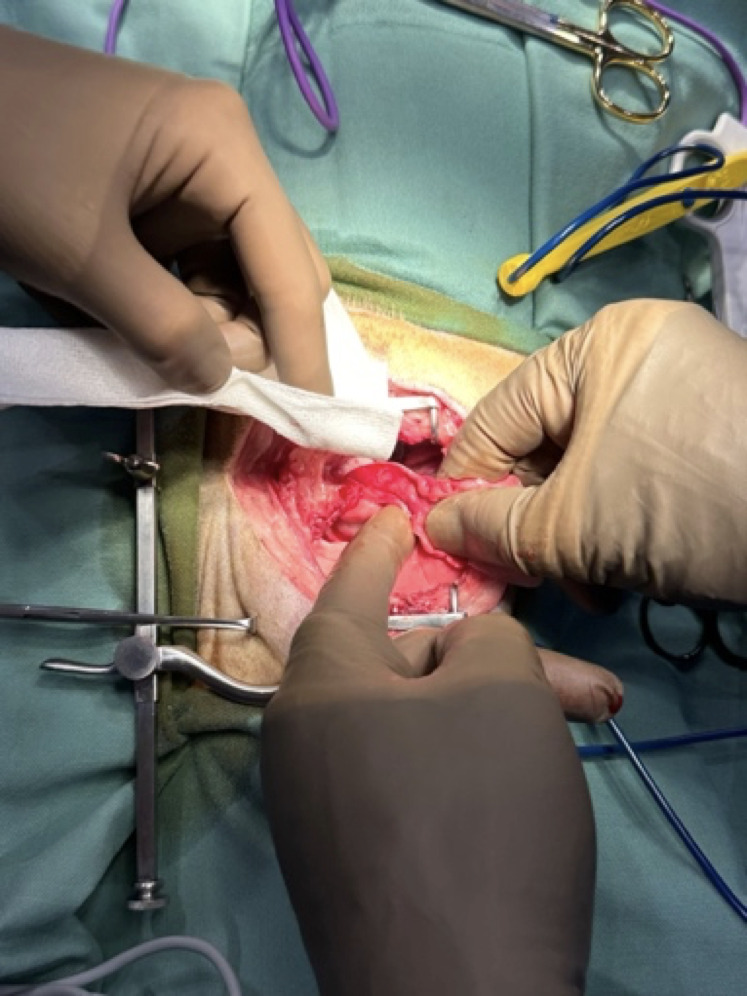

食道の腫瘍

食道の腫瘍は非常に稀ですが、食道内が閉塞を起こすことでご飯を食べることが困難になったり、嚥下時の不快感や吐出などの症状を認めます。

食道の腫瘍には扁平上皮癌、骨肉腫、繊維肉腫などが認めらます。

手術の適応される症例では開胸手術により手術を行うこともあります。また広範囲に及ぶ手術では再建のための組織の使用や代用物について様々な報告がされています。